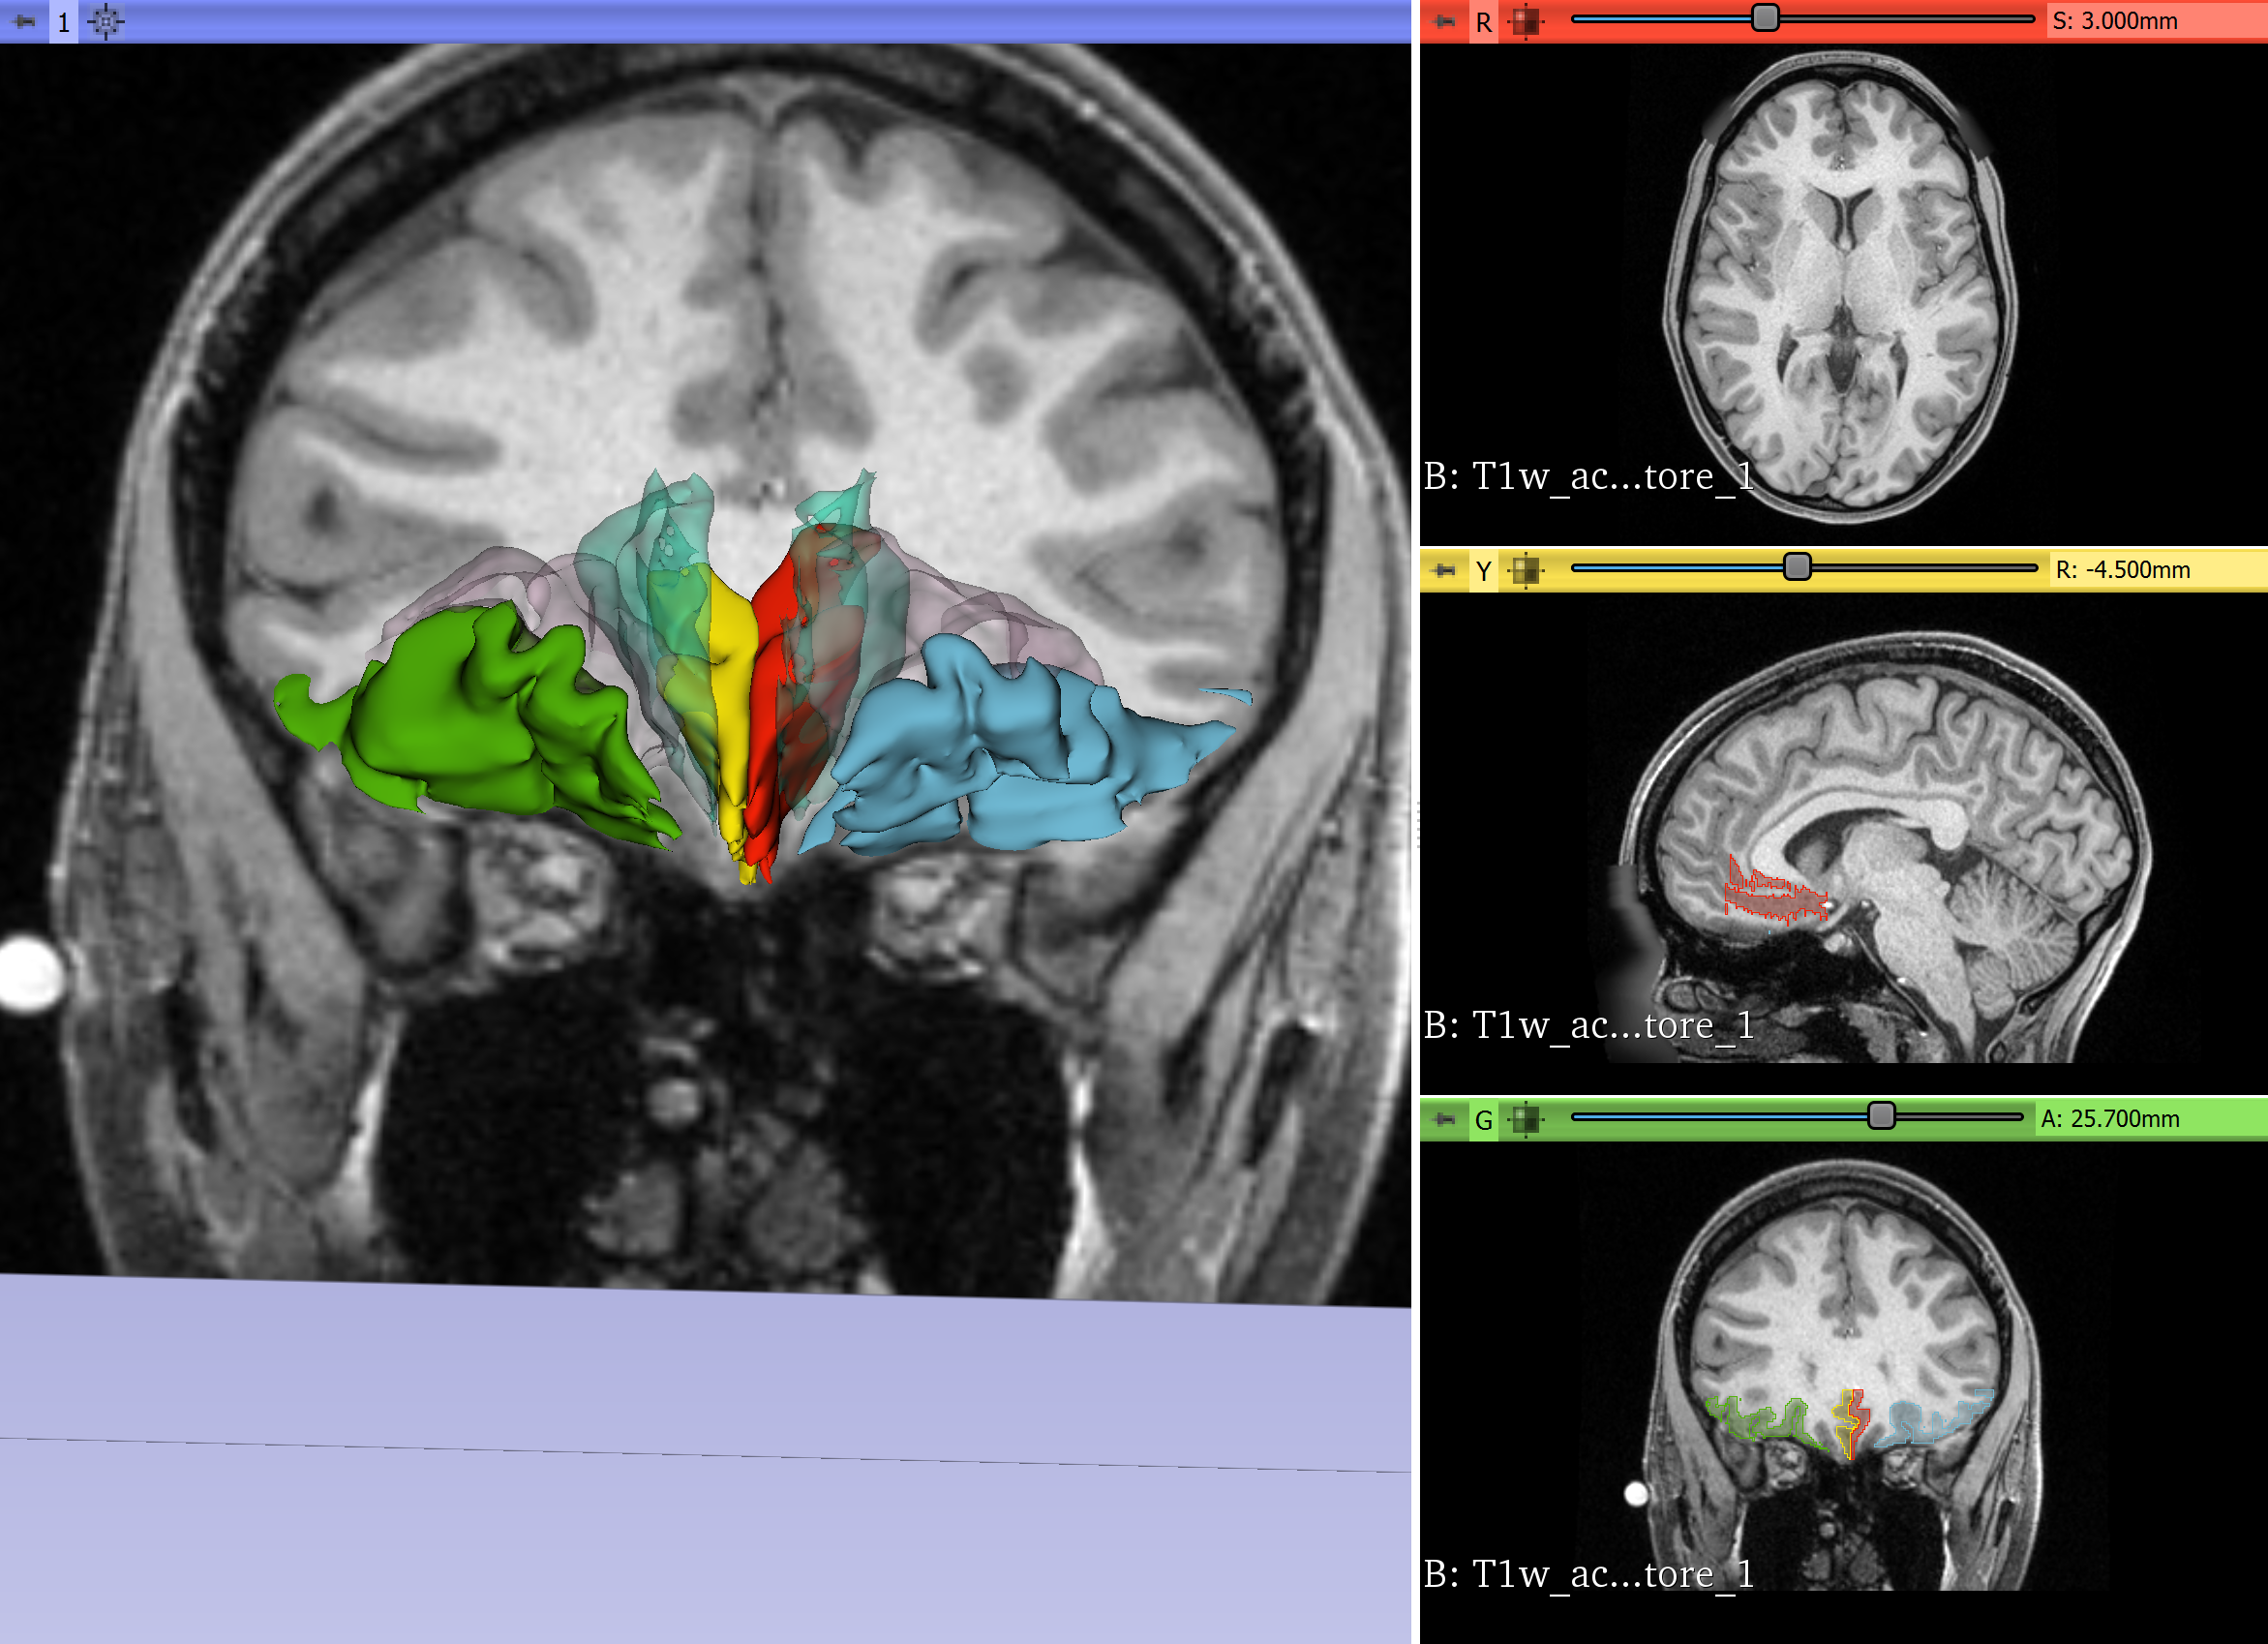

Quantitative Analysis of Human Orbitofrontal-subgenual Circuitry

The orbitofrontal-subgenual circuitry is important for the treatment of major depressive disorder (MDD) using non-invasive treatments in psychiatry, such as transcranial magnetic stimulation (TMS) or invasive neurosurgical approaches such as Deep Brain Stimulation (DBS). The anatomical structures involved in this circuitry are the orbitofrontal cortex, Brodmann’s area 11(BA 11), the Subcallosal area, BA 25 and the fiber tract that interconnects these two cortical areas, namely the frontopolar bundle. The two cortical areas of this circuitry can be targets for TMS procedures or DBS interventions.

- We will segment the orbitofrontal cortex and the subcallosal area using SLICER in the individual subject brain using T1 MRI data.

- We will connect these two cortical regions using the tractographic white matter query language (WMQL) software on diffusion MRI data of the same subject.

- Segmentation of orbitofrontal cortex and subcallosal area successfully performed on T1 data.

- Whole brain DMRI tractography successfully performed.

- Diffusion and Structural data registered.

- WMQL query performed.

Illustrations